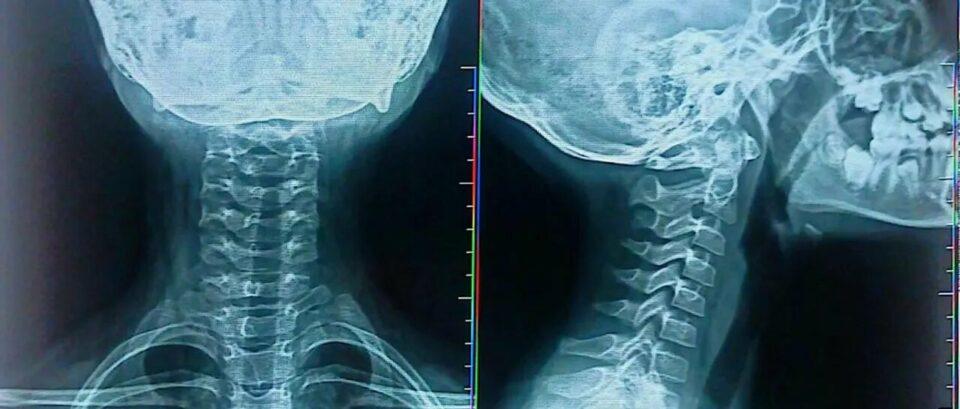

Cochabamba, 15 de abr 2025 (ATB Digital).- Una niña de primaria en Cochabamba sufrió una lesión en el cuello tras ser empujada por su maestro durante una clase en una unidad educativa de la zona sur. La menor fue atendida médicamente y está fuera de peligro. Las autoridades investigan el hecho, mientras la comunidad exige sanciones para el docente agresor.